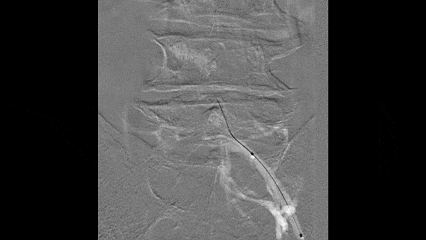

超声引导下穿刺左侧腘静脉置入鞘管

行左下肢静脉及髂静脉造影

尝试通过腘静脉、股浅静脉、髂股段静脉病变

发现股浅静脉近端闭塞,通过侧支与股深静脉沟通

髂静脉闭塞,盆腔侧支静脉形成